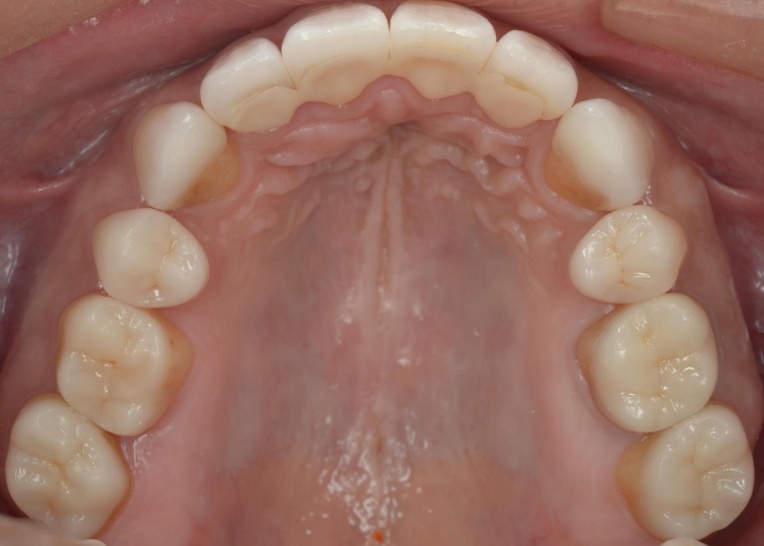

治療前

治療中

治療後